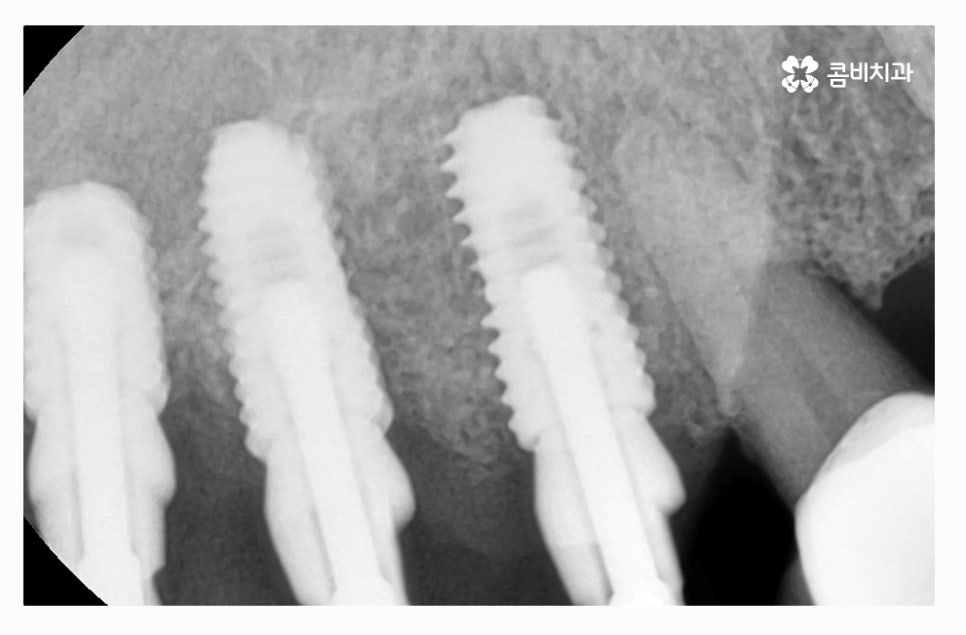

임플란트를 한꺼번에 식립해야 하기 때문에 3D CT 등을 활용한

정밀검진부터 철저하게 해야 하고 식립 각도 하나하나에

철저해야 하기 때문에 의료진의 경험과 실력이 중요한 시술이라 할 수 있어요.

임플란트의 치료 기간은 개개인의 잇몸과 구강 상태 등에 따라

다르며 임플란트와 잇몸 뼈가 튼튼하게 결합이 돼야 하기 때문에

빠르고 저렴한 방법이 우선시 되기보다는 개개인의

건강 상태를 충분히 고려하고 정품 사용은 기본이며